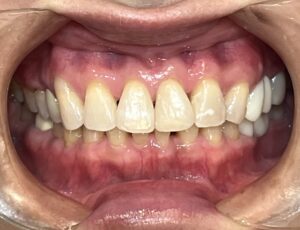

最近のマウスピース矯正(インビザラインGO)の症例をご紹介いたします。

Before after

写真を比較してみると、

前歯の捻じれや、重なりが とてもキレイに改善されましたね!

こちらの患者様は、矯正後にホワイトニングも行ったため、

歯の色もトーンアップしました☆